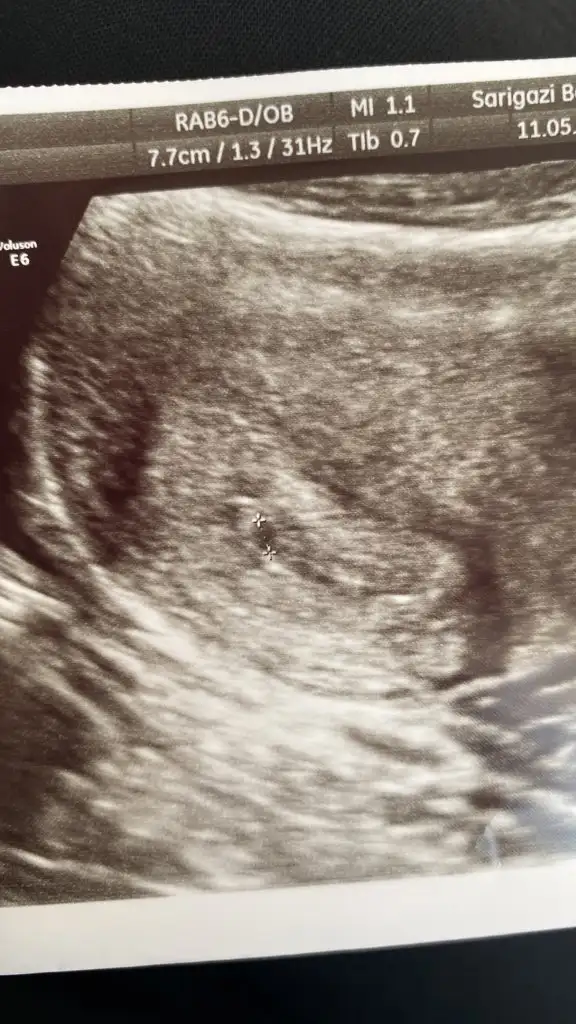

Merhaba kızlar ben geçen hafta salı günü öğrendim beta 1483’le 🥹 Çarşamba günü doktora gittim keseye benziyor dedi ama sizce kese mi bu doktor da emin olamadı çünkü. Yarın yine kontrolüm var çok heyecanlıyım ama korkuyorum da 🥹🥹

Eklentiler

• AEAC0444-127B-4751-B482-4B017794092C.webp

AEAC0444-127B-4751-B482-4B017794092C.webp

46,2 KB · Görüntüleme: 73